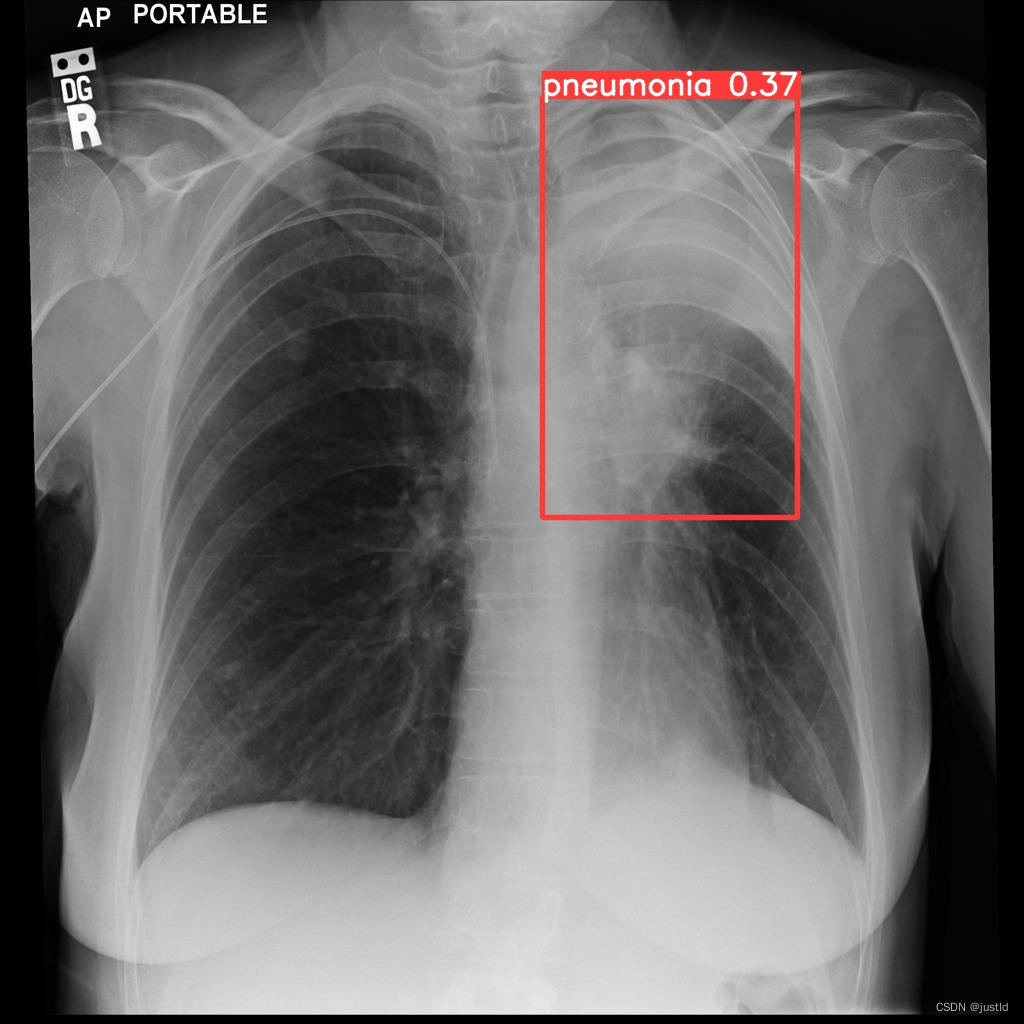

检测结果如下图: